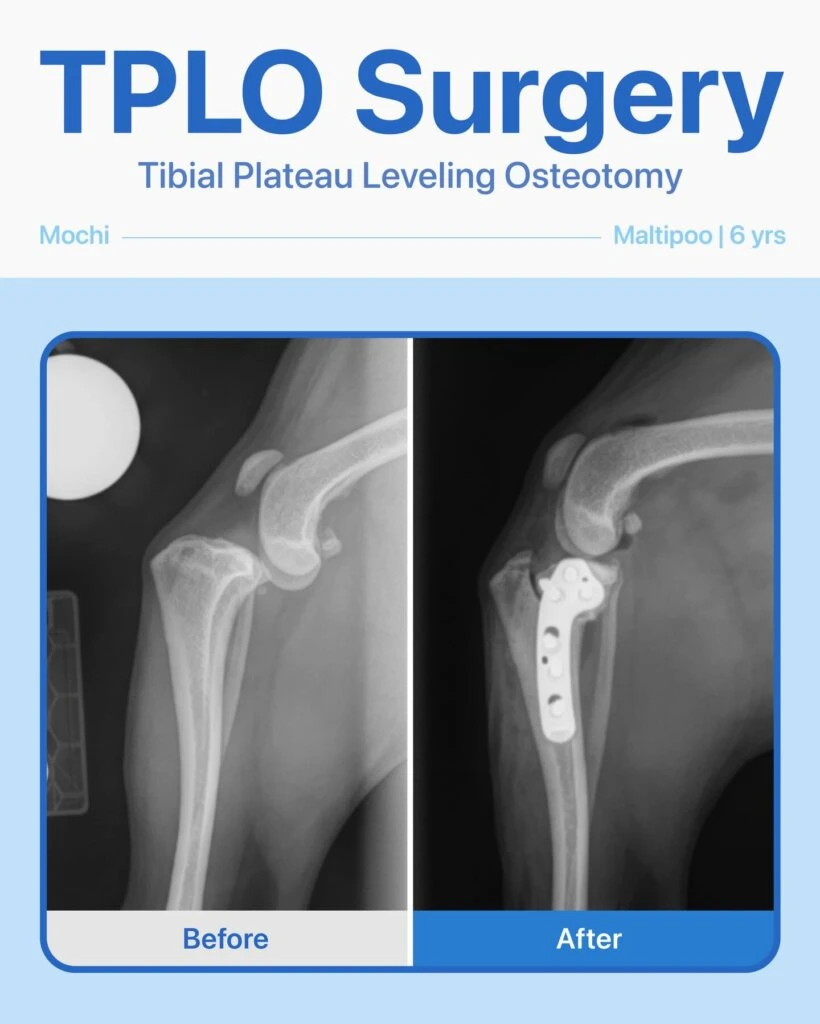

After a jump gone wrong, 6-year-old Mochi the Maltipoo began limping on his back left leg and came to us for care. Mochi’s owner first took him to an emergency hospital, where a torn ligament was suspected, and then came to our team for a second opinion. After a thorough orthopedic exam and radiographs, we confirmed that Mochi needed TPLO surgery as soon as possible.